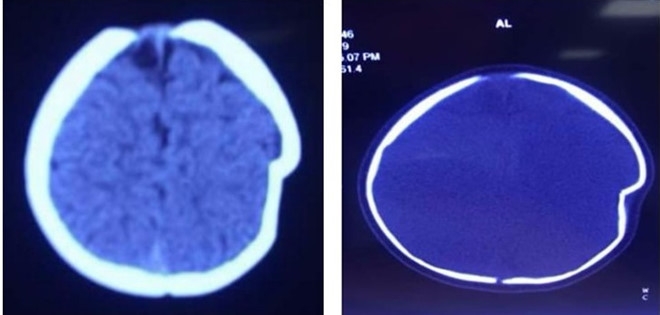

| Tại đây, bệnh nhi được chẩn đoán: lún sọ thái dương đỉnh trái. |

Mẹ của bé (trú tại ở Thanh Thủy, Phú Thọ) cho biết tai nạn xảy ra khi chị để con ngồi trên xe tập đi một mình và không kiểm tra mối dây buộc khiến chiếc xe lao xuống sân với ở độ cao khoảng 1 m. Cú va chạm mạnh với mặt đất đã khiến chóp đầu trái của bé bị lún sâu 1 cm.

Theo bác sĩ Hà Xuân Tài, Phó Khoa Ngoại Thần kinh, lún sọ pingpong thường gặp ở trẻ nhũ nhi dưới 1 tuổi. Nguyên nhân thường do tai biến sinh có thủ thuật, hay trẻ bị ngã khi tập đứng, tập đi và trẻ bị ngã ở độ cao. Vị trí thường gặp hộp sọ là vùng đỉnh.

Do ở trẻ nhũ nhi hộp sọ có khả năng tự điều chỉnh tốt nên hiếm khi phải mổ cấp cứu ngay, trừ những trường hợp lún sọ mức độ nhiều, tổn thương rách màng cứng và tổn thương não. Tuy nhiên, cha mẹ thường rất lo lắng và yêu cầu được mổ ngay vì liên quan đến thẩm mỹ hộp sọ và sợ ảnh hưởng đến thần kinh của trẻ về sau.

Với trường hợp bé 8 tháng này, các bác sĩ đã tiến hành phẫu thuật để nâng xương lún vào ngày 4/9. Đến chiều 12/9, khi sức khỏe ổn định trở lại, bé được xuất viện.